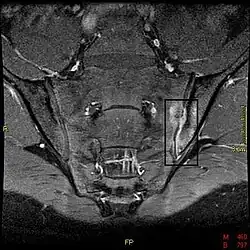

Das Kreuzbein-Darmbeingelenk ist das „Schlüsselgelenk“ der Spondylitis ankylosans. Bei circa 99 Prozent der Patienten gibt sich die Erkrankung radiologisch zuerst an den Kreuzbein-Darmbeingelenken zu erkennen. Charakteristisch ist eine bilaterale Kreuzbein-Darmbeingelenk-Arthritis mit dem Nebeneinander von Knochenabbau und -anbau, subchondralen Sklerosen und beginnender Ankylose (radiologische Graduierung 1–4). Eine gesicherte AS besteht, wenn eine unilaterale Sakroiliitis Grad 3–4 oder bilaterale Sakroiliitis Grad 2–4 und ein klinisches Kriterium bestehen. Laboruntersuchungen sind bei der SA weniger hilfreich. Nur in circa 30–40 Prozent der Fälle finden sich Erhöhungen der Blutsenkung oder des C-reaktiven Proteins. Mit der Erkrankung einhergehende Bewegungseinschränkungen können durch einfache Untersuchungen genauer bestimmt werden (Schober-Maß, Ott-Maß,[21] Menell-Zeichen, Kinn-Brustbein-Abstand, Hinterkopf-Wand-Abstand, atemabhängige Änderung des Brustumfangs).

Bildgebung

Erosion, reaktive Verkalkungen, und Verknöcherung der Articulatio sacro-iliaca waren seit den 1930er Jahren die ersten pathognomonische Symptome der Spondylitis ankylosans. In späteren Stadien kann es zu Knochenspangen zwischen benachbarten Wirbeln und Verknöcherungen des Wirbelkörperbandapparates kommen. Die Verknöcherung der Wirbelsäule ist auf Röntgenbildern gut zu erkennen und wird wegen ihrer markanten Form auch als Bambuswirbelsäule bezeichnet.

Die modifizierten New-York-Kriterien (1984) waren lange Zeit der Goldstandard für die Diagnose von Morbus Bechterew. Außer den klinischen Symptomen (tiefsitzender Rückenschmerz und Steifheit für mehr als drei Monate, verbessert durch Bewegung) gehörten dazu die im Röntgenbild sichtbaren Zeichen einer beidseitigen Sakroiliitis Grad 2–4, oder einseitig Grad 3–4. Heutzutage werden die meisten Fälle frühzeitig durch die Kernspintomographie dargestellt, die die Veränderungen wesentlich früher zeigt als klassische Röntgenaufnahmen.